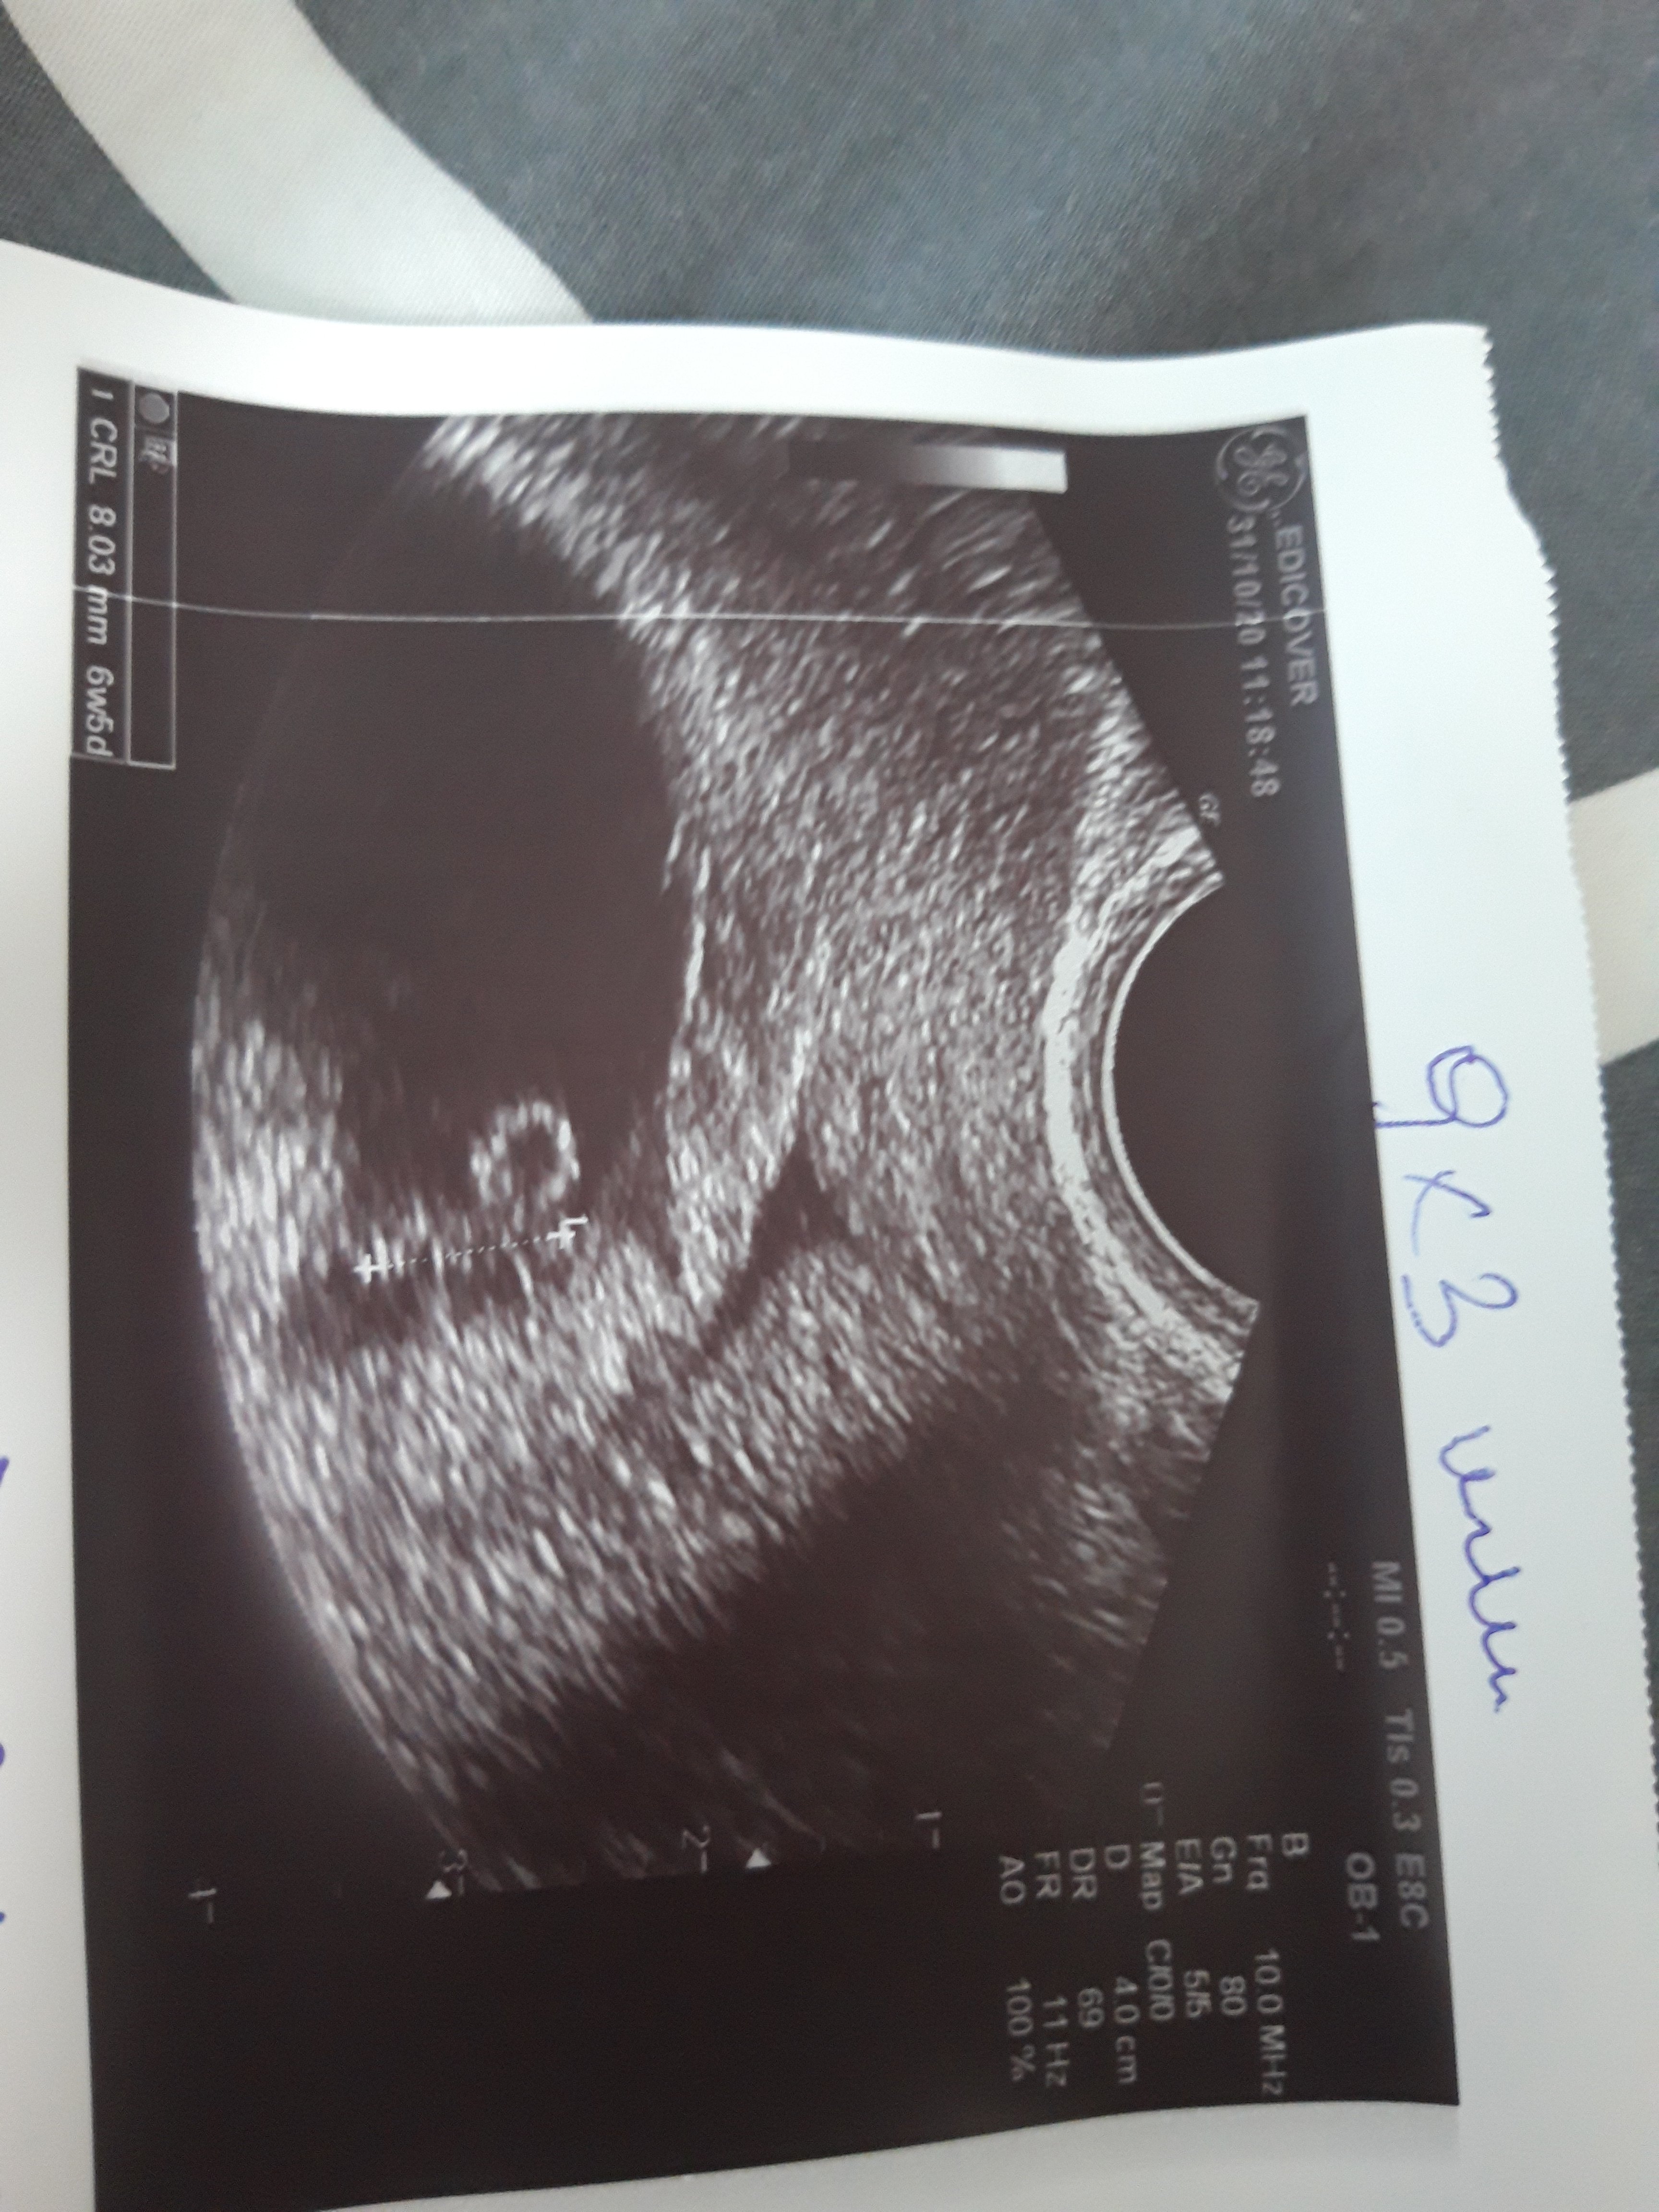

Dziewczyny ale jestem zestresowana :( Wczoraj wieczorem zobaczylam na papierze delikatne brazowe plamienie, oczywiscie mnie to przerazilo i umowilam sie na dzis do lekarza.

Z jednej strony ok, bo serduszko bije i zarodek sie rozwija , ale lekarz zauwazyl, ze delikatnie kosmykowka się odkleja w jednym miejscu :( Kazal leżeć i brac luteine dopochwowo, za tydzien mam kontrole.

Czy ktoras z Was miala podobna sytuacje?Zobacz załącznik 1194852